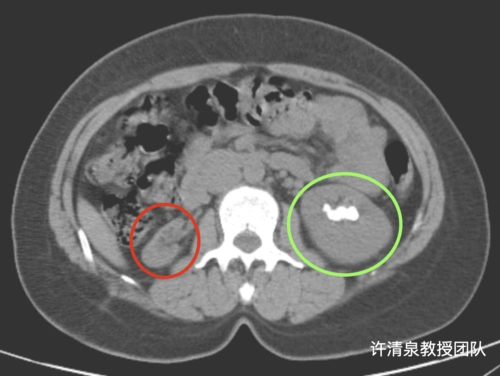

图16 左肾结石

ct片上显示肾里塞满了结石

这类肾脏致密影不是单纯肾结石

ct影像显示肾脏被巨大结石霸占.长沙晚报通讯员 胡薇华 陈昊 供图

左肾积水结石影.

泌尿系统结石之肾结石ct表现 - 好大夫在线